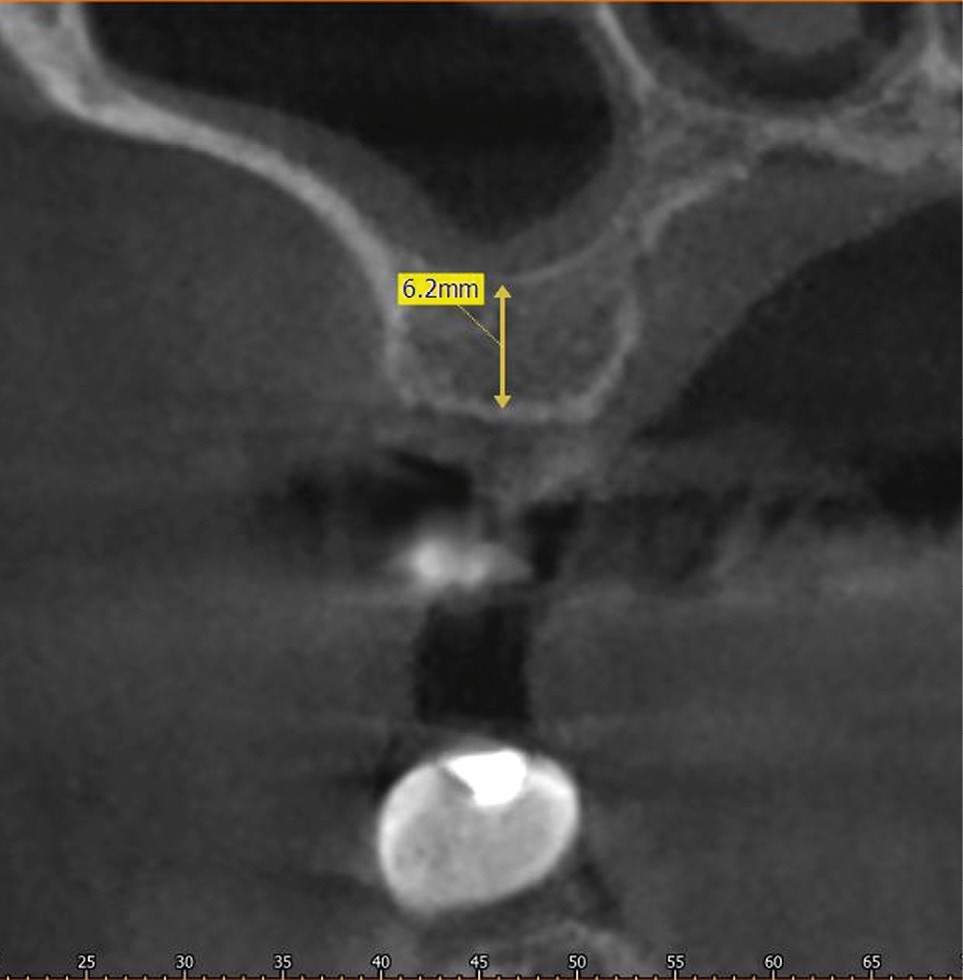

Cette procédure chirurgicale est indiquée lors de la pose d’implant dans le secteur maxillaire postérieur lorsque l’étude radiologique montre une hauteur osseuse insuffisante.

Pour sa mise en œuvre, deux techniques sont décrites dans la littérature et largement utilisées par les praticiens. La première est le soulevé sous-sinusien par voie latérale, ou « external sinus lift ». Cette méthode est actuellement préconisée quand la hauteur d’os résiduelle est inférieure à 4 mm. La seconde technique est une approche moins invasive, le soulevé crestal, désigné communément par les termes « ostéotomie de Summers ». Il est indiqué quand la hauteur d’os est suffisante pour assurer une stabilité primaire de l’implant, avec des gains limités en hauteur, variables selon les auteurs.